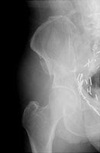

MALGAIGNE

- Fracture of the ilium near the sacroiliac joint with displacement of the symphysis, or a dislocation of the sacroiliac joint with fracture of both ipsilateral pubic rami

- unstable pelvis